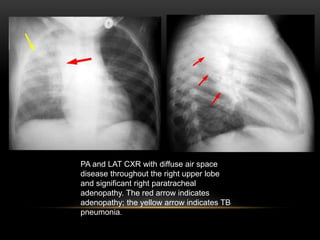

PA and LAT CXR with diffuse air space

disease throughout the right upper lobe

and significant right paratracheal

adenopathy. The red arrow indicates

adenopathy; the yellow arrow indicates TB

pneumonia.